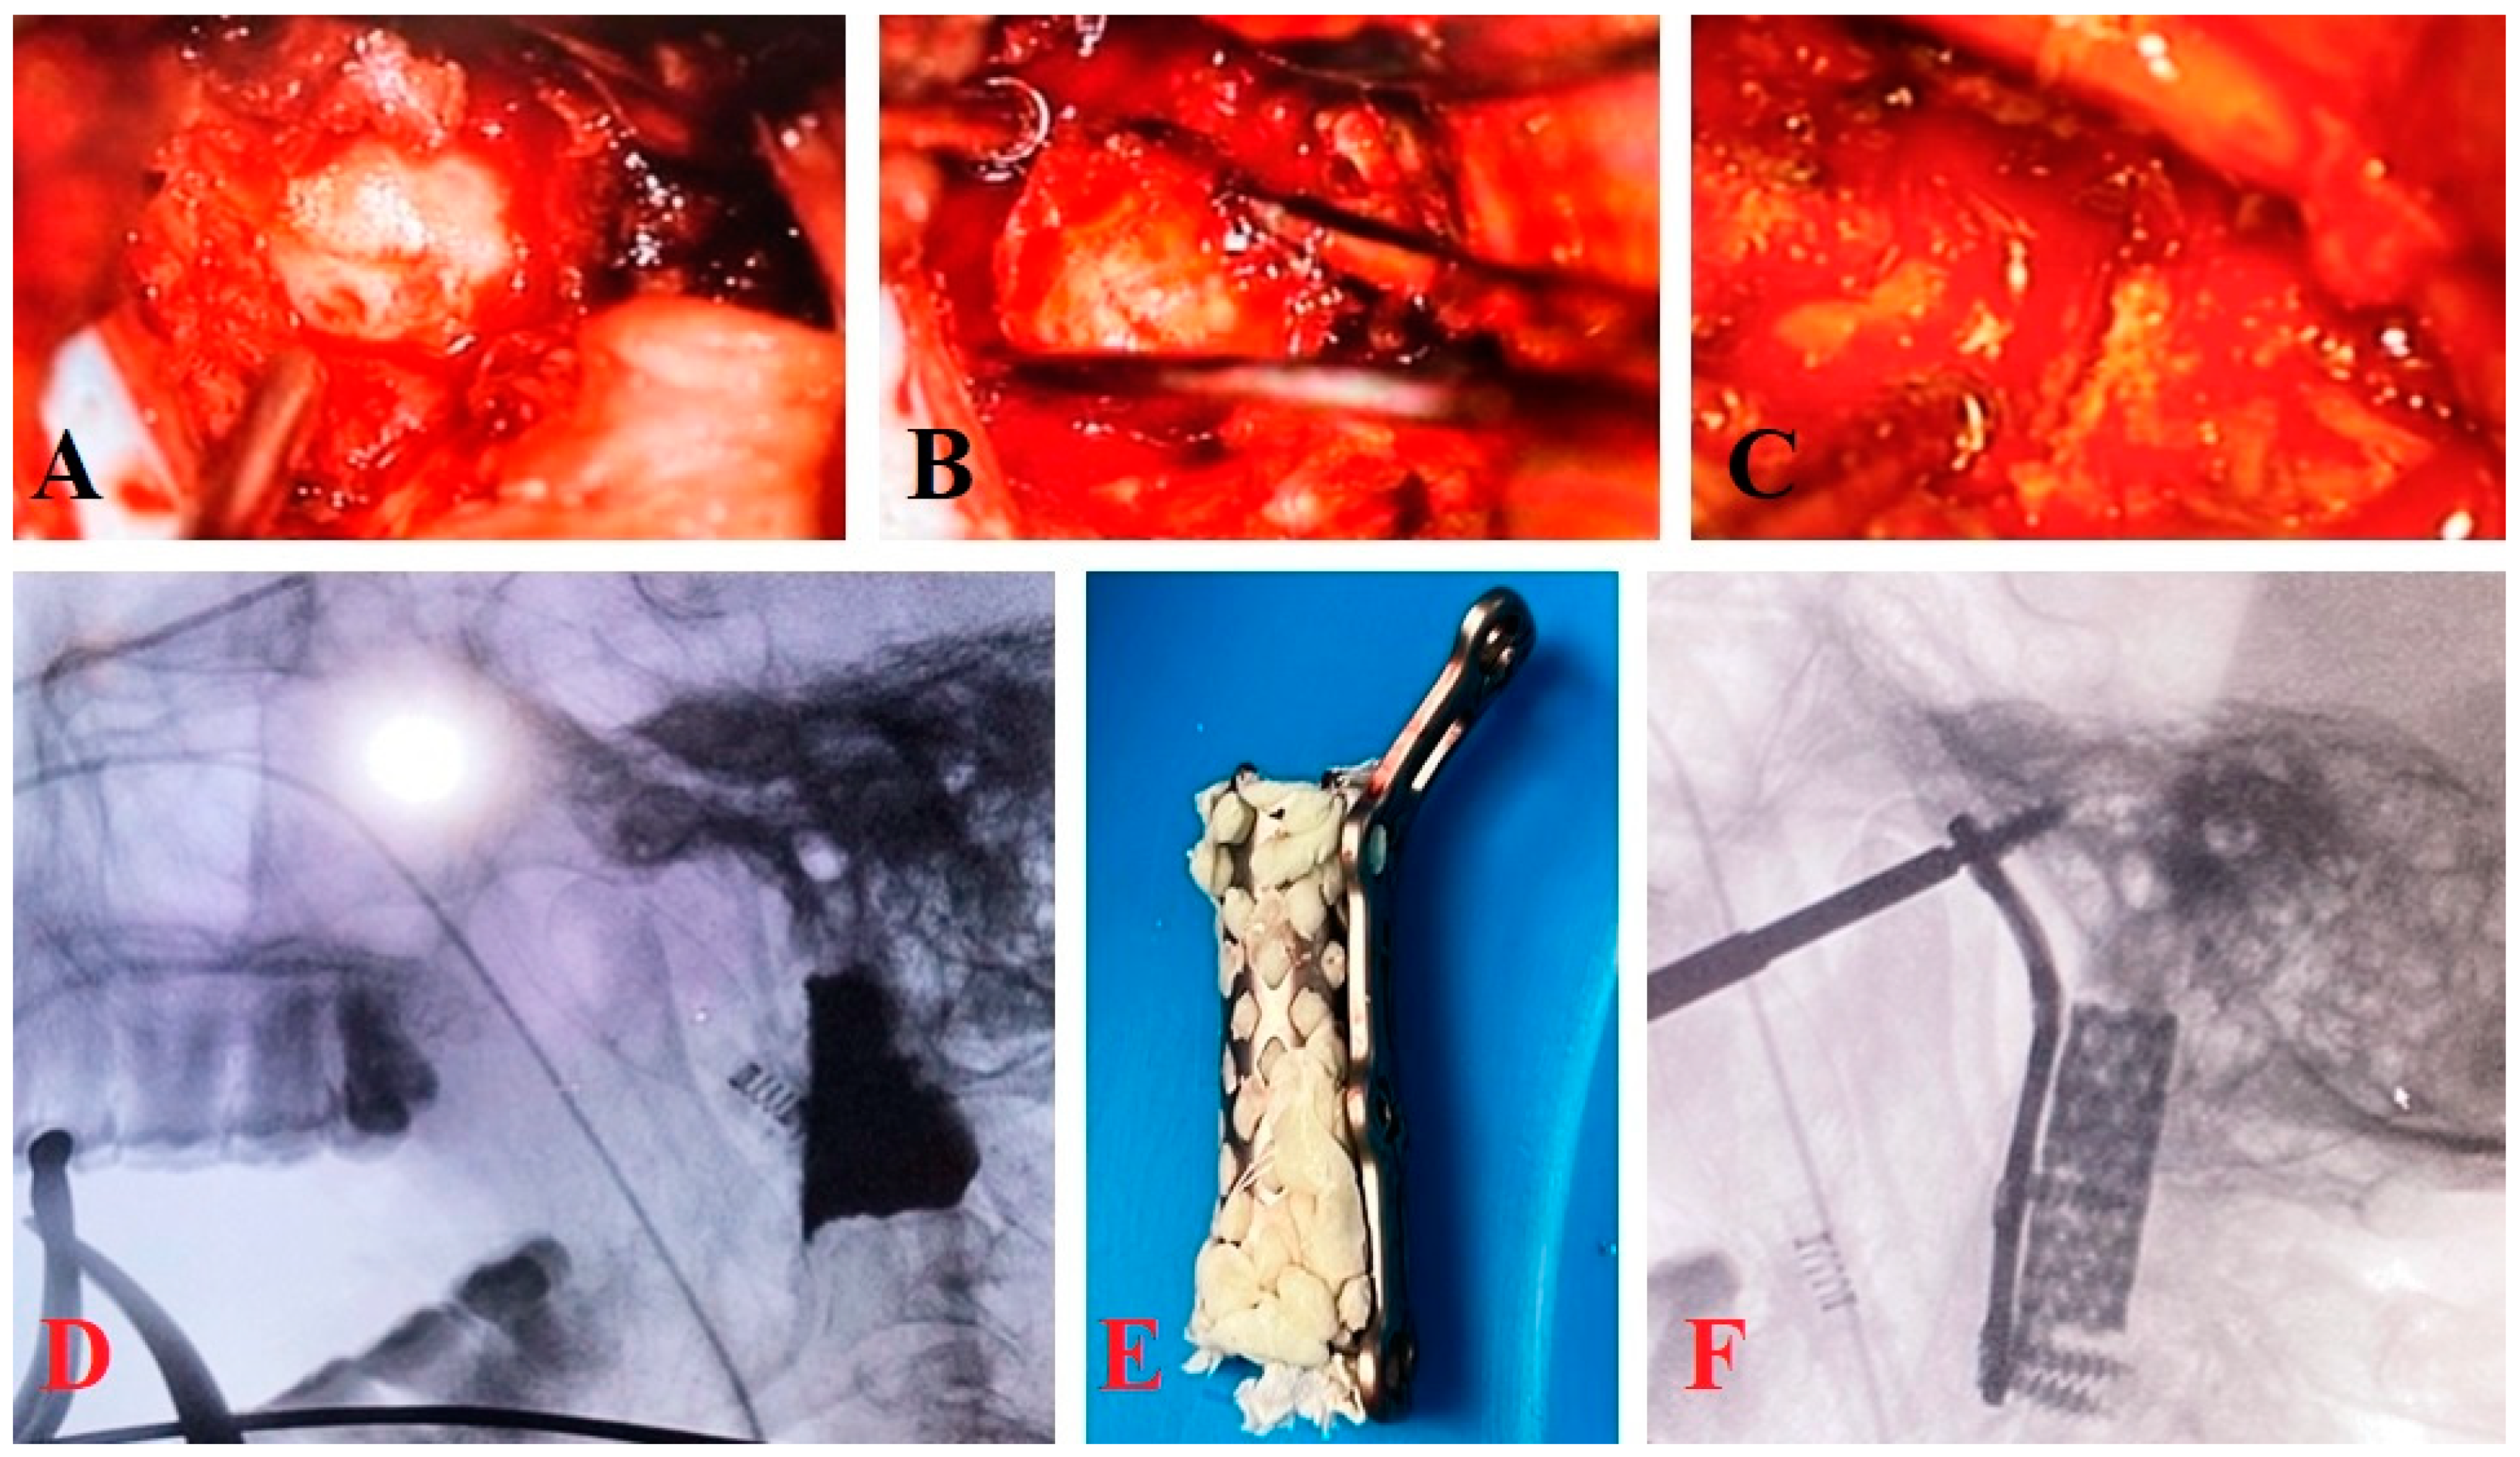

Surgical Technique

3.1.1. Clinical Case 1

3.1.2. Clinical Case 2

3.1.3. Clinical Case 3

3.3. Surgical Technique and Radiological Follow-Up